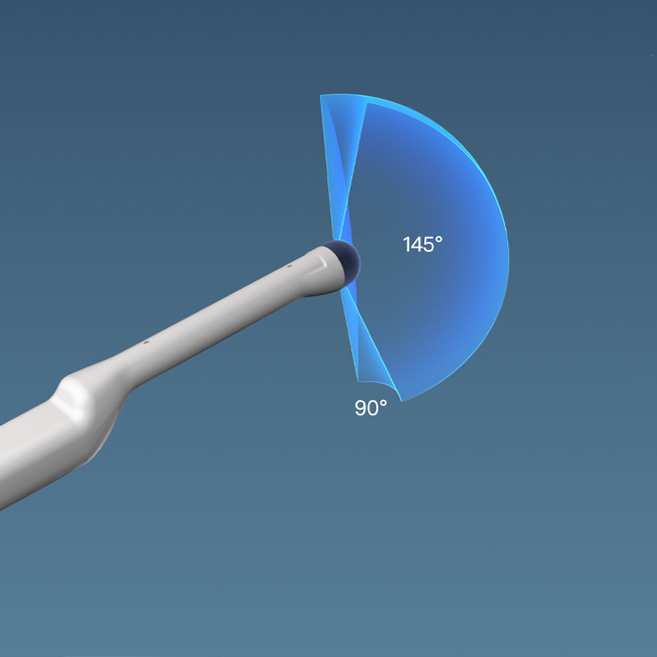

KOELIS® offers a 3D side-fire ultrasound probe, probe holder and guides that improve visualization and during transperineal prostate biopsy.

KOELIS® 3D ultrasound end-fire probe and accessories enable optimal visualization and targeted interventions via transrectal access.